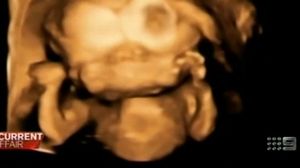

Bebelusul nenascut al sotilor Howie are o singura inima, patru membre si doua capete unite. Medicii i-au recomandat mamei sa faca avort fiindca sansele de supravietuire ale micutului sunt foarte mici. Acum doua luni, un copil, nascut in India cu aceeasi malformatie a murit, scrie Daily Mail.